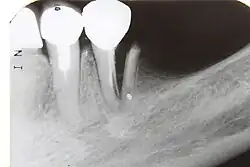

| 7) Root fracture | Mobile or displaced crown segment Tender tooth that may be bleeding from the gum Tooth may be discoloured (red or grey) | Fracture line involving the root will be seen as well as the direction | If displaced, reposition tooth and check the position with an x-ray Flexible splint used to stabilise tooth for at least 4 weeks and then reassess tooth stability Monitor healing for at least 1 year to assess the status of the pulp Root canal treatment will be needed if pulp necrosis develops (this occurs in ~20% of root fractures) | 4 weeks: splint removal, clinical and radiographic examination 6–8 weeks: clinical and radiographic examination 4 months: splint removal in cervical third fractures, clinical and radiographic examination 6 months: clinical and radiographic examination 1 year: clinical and radiographic examination 5 years: clinical and radiographic examination |